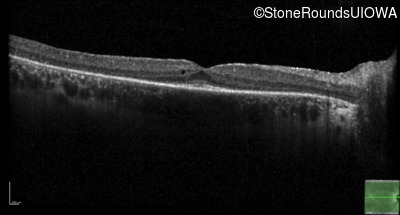

Optical Coherence Tomography - Left -

20/20

Exemplar / OCT Stack